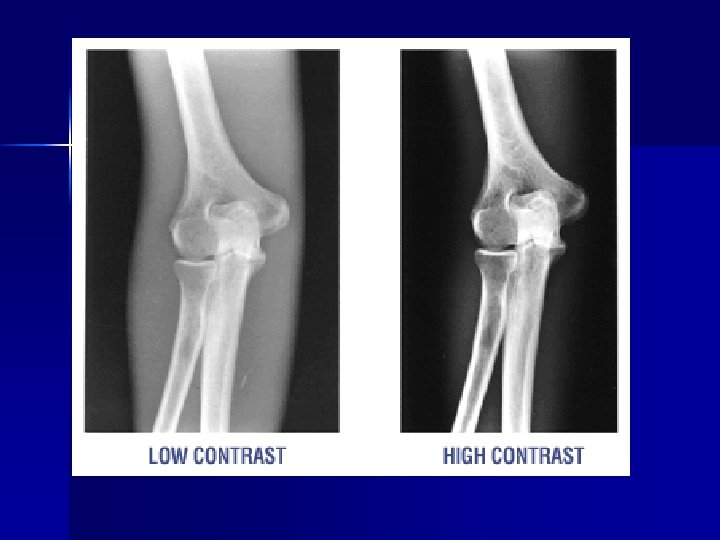

Producing optimal radiographs Contrast Scale Long scale short scale

Scale of Contrast? Which one is “better” How does the k. Vp affect these images?

Short Scale vs. Long Scale